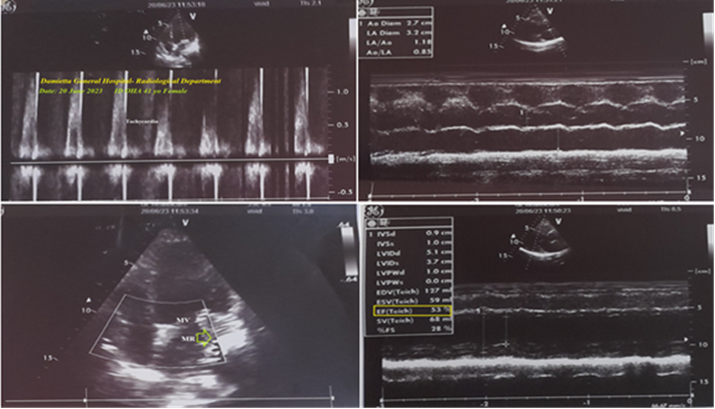

A 41-year-old married female housewife, patient, was presented to the intensive care unit (ICU) with palpitations, acute non-specific chest pain, and dizziness. Cough, headaches, and generalized body pain were associated symptoms. The patient has a history of diabetes mellitus 12 years ago, on long-acting insulin. She also has a history of bronchial asthma 20 years ago on intermittent anti-asthmatic medications. Upon general physical examination, the patient had tachypnea and distressed respiration, with a regular pulse rate (junctional tachycardia (JT) with VR of 165), blood pressure (BP) of 110/80 mmHg, respiratory rate of 25 bpm, a temperature of 36°C, and a pulse oximeter of oxygen (O2) saturation of 97%. No more relevant clinical data were noted during the clinical examination. The patient refused the referral for admission to the intensive care unit (ICU). He was initially managed at the ICU, with a junctional tachycardia, diabetes, non-specific chest pain, and Brugada syndrome. Initially, the patient was treated with O2 inhalation via an oxygen system line (100%, using a normal mask, 5L/min). The initial ECG tracing was performed on the initial presentation to the ICU, with one and a half calibration showing junctional tachycardia, normal axis, and coving-like ST-segment elevations in the aVR, V1, and V2 leads. There is a loose lead artifact in the V5 lead (Figure 1A). The second ECG tracing was taken within 3 minutes of the above ECG tracing, with one and a half calibration showing junctional tachycardia, interlacing of premature junctional complexes in V1 and V2 leads, with the same changes as above. But with AC artifacts and Wavy triple sign (Yasser's sign) in V6 lead (Figure 1B). The patient was treated with amiodarone IV bolus (300 mg IV over 20 minutes, then a continuous IVI at a rate of 1 mg/min for 6 hours). The patient was monitored hourly for vital signs and O2 saturation. The third ECG tracing was taken within 22 hours of the above ECG tracing, with one and a half calibration showing sinusoidal AF, normal axis, and disappearance of the above coving-like ST-segment elevations (Figure 1C). Amiodarone IV was given as a maintained dose, Diltiazem tablets (60mg, OD), SC Enoxaparin 40 mg, OD, and Warfarin tablet (5 mg, OD) were added. There is a new mild fever (temp of 38.5°C), tachypnea, dry cough, and frequent micturition. Urine analysis on the second day of ICU admission showed: pus over 50, RBCs: 10-12, and epithelial cells (++). The fourth ECG tracing was taken within 42 hours of the above ECG tracing, showing sinus tachycardia, normal axis, a coving-like ST-segment elevations in the aVR, V1, and V2 leads (Figure 1D). The fifth ECG tracing was taken within 6 hours of the above ECG tracing, showing sinus tachycardia, right axis deviation, with coving-like ST-segment elevations in I and aVL leads. There is a loose lead artifact in V2 lead (Figure 1E). Cefotaxime vials (1 gm IV BID) and paracetamol (500 mg TID as needed) were added. The sixth ECG tracing was taken within 1 minute of the above ECG tracing, showing sinusoidal AF, right axis deviation, with coving-like ST-segment elevations in the I and aVL leads. There is a loose lead artifact in V2 lead (Figure 1F). The seventh ECG tracing was taken within 1 minute of the above ECG tracing, showing sinusoidal AF, right axis deviation, with coving-like ST-segment elevations in I and aVL leads. There is a loose lead artifact in the V2 lead (Figure 1G). The eighth ECG tracing was taken within 24 hours of the above ECG tracing, showing sinusoidal AF, right axis deviation, with coving-like ST-segment elevations in the I and aVL leads. There is sagged ST-segment depression in the V4-6 leads (Figure 1H). The ninth ECG tracing was taken within 7 hours of the above ECG tracing, showing sinusoidal AF with normal axis (Figure 1I). The tenth ECG tracing was taken within 5 days of the above ECG tracing, with one and a half calibrations, showing junctional tachycardia, left axis deviation, with coving-like ST-segment elevations in the III, aVR, and V1 leads. There is a retrograde P wave in V6 lead (Figure 1J). The eleventh ECG tracing was taken within 8 hours of the above ECG tracing, showing sinusoidal AF, right axis deviation, with coving-like ST-segment elevations in I and aVL leads. There is equivocal QRS in the aVR lead (Figure 1K). The chest X-ray film PA view performed on the initial presentation to the ICU shows tail-like outward apical elongation. There are mild right and left consolidation opacities (Figure 2A). The plain film of chest CT performed on the initial presentation to the ICU showed tail-like outward apical elongation with a narrow lower black recess separating the left diaphragmatic surface and lower surface of the right heart (Figure 2B). Serial cuts of chest CT were done on the initial presentation to the ICU, showing no abnormalities (Figure 2C). Serial cuts of brain CT were done on the initial presentation to the ICU, showing no abnormalities (Figure 2D). The echocardiography was done within 4 days after the ICU presentation, showing tachycardia, mild mitral regurgitation, and a good LV systolic function of an EF of 53% (Figure 3). The initial laboratory: complete blood count (CBC); Hb was 11.3 g/dl, RBCs; 5.37*103/mm3, WBCs; 12.0*103/mm3 (Neutrophils; 53.7 %, Lymphocytes: 36.1%, Monocytes; 8.2%, Eosinophils; 0% and Basophils 0%), Platelets; 327*103/mm3. CRP was 6.0. SGPT was (26.7 U/L). Serum albumen was 4.2 gm/dl. Serum creatinine was (0.97 mg/dl). RBS was (254 mg/dl). D-dimer was 0.3ug/ml. ABG was done in the third day; (PH; 7.41, PCO2; 49.6 mmHg, HCO3; 31.8 mmHg, So2; 96%, and PaO2; 78 mmHg). INR was 1.04 with a prothrombin time of 13.08 seconds. The associated electrolytes in the ABG profile: Plasma sodium was 160 mmol/L. Serum potassium was (3.2 mmol/L). Serum ionized calcium was (1.01 mmol/L). The CBC was repeated in the third day; Hb was 11.2 g/dl, RBCs; 5.33*103/mm3, WBCs; 13.7*103/mm3 (Neutrophils; 67.6 %, Lymphocytes: 27.6%, Monocytes; 4.8%, Eosinophils; 0% and Basophils 0%), Platelets; 322*103/mm3. The troponin initial test was negative. On the ninth day; The CBC: Hb was 10.8 g/dl, RBCs; 5.17*103/mm3, WBCs; 13.8*103/mm3 (Neutrophils; 63.7 %, Lymphocytes: 31.4%, Monocytes; 4.9%, Eosinophils; 0% and Basophils 0%), Platelets; 210*103/mm3. CRP was 12.0. SGPT was (31.0 U/L). Serum creatinine was (0.6 mg/dl). Rheumatoid factor was negative. Migratory Brugada syndrome, variable interlacing arrhythmias, ECG axis deviations, and mild chest and urinary tract infections in a diabetic patient are the most probable diagnosis. Within eleven days of the above at-ICU management, the patient finally showed nearly complete clinical and ECG improvement. The patient was continued on Diltiazem tablets (60 mg, OD), Amiodarone tablets (200 mg, OD), Warfarin (5mg, OD), long-acting insulin, oral calcium, and Vitamin-D preparations for 14 days with further recommended cardiac and urological follow-up.

Figure 3: Echocardiography was taken within 4 days after the ICU presentation, showing tachycardia, mild mitral regurgitation (lime arrow), and a good LV systolic function of an EF of 53% (lime-rectangular).